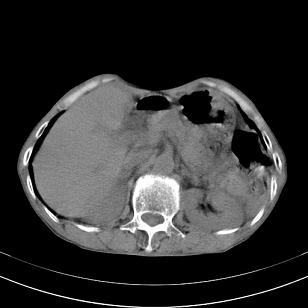

标题: 男,65岁,反复右上腹痛, [打印本页]

标题: 男,65岁,反复右上腹痛,

胃镜提示十二指肠占位